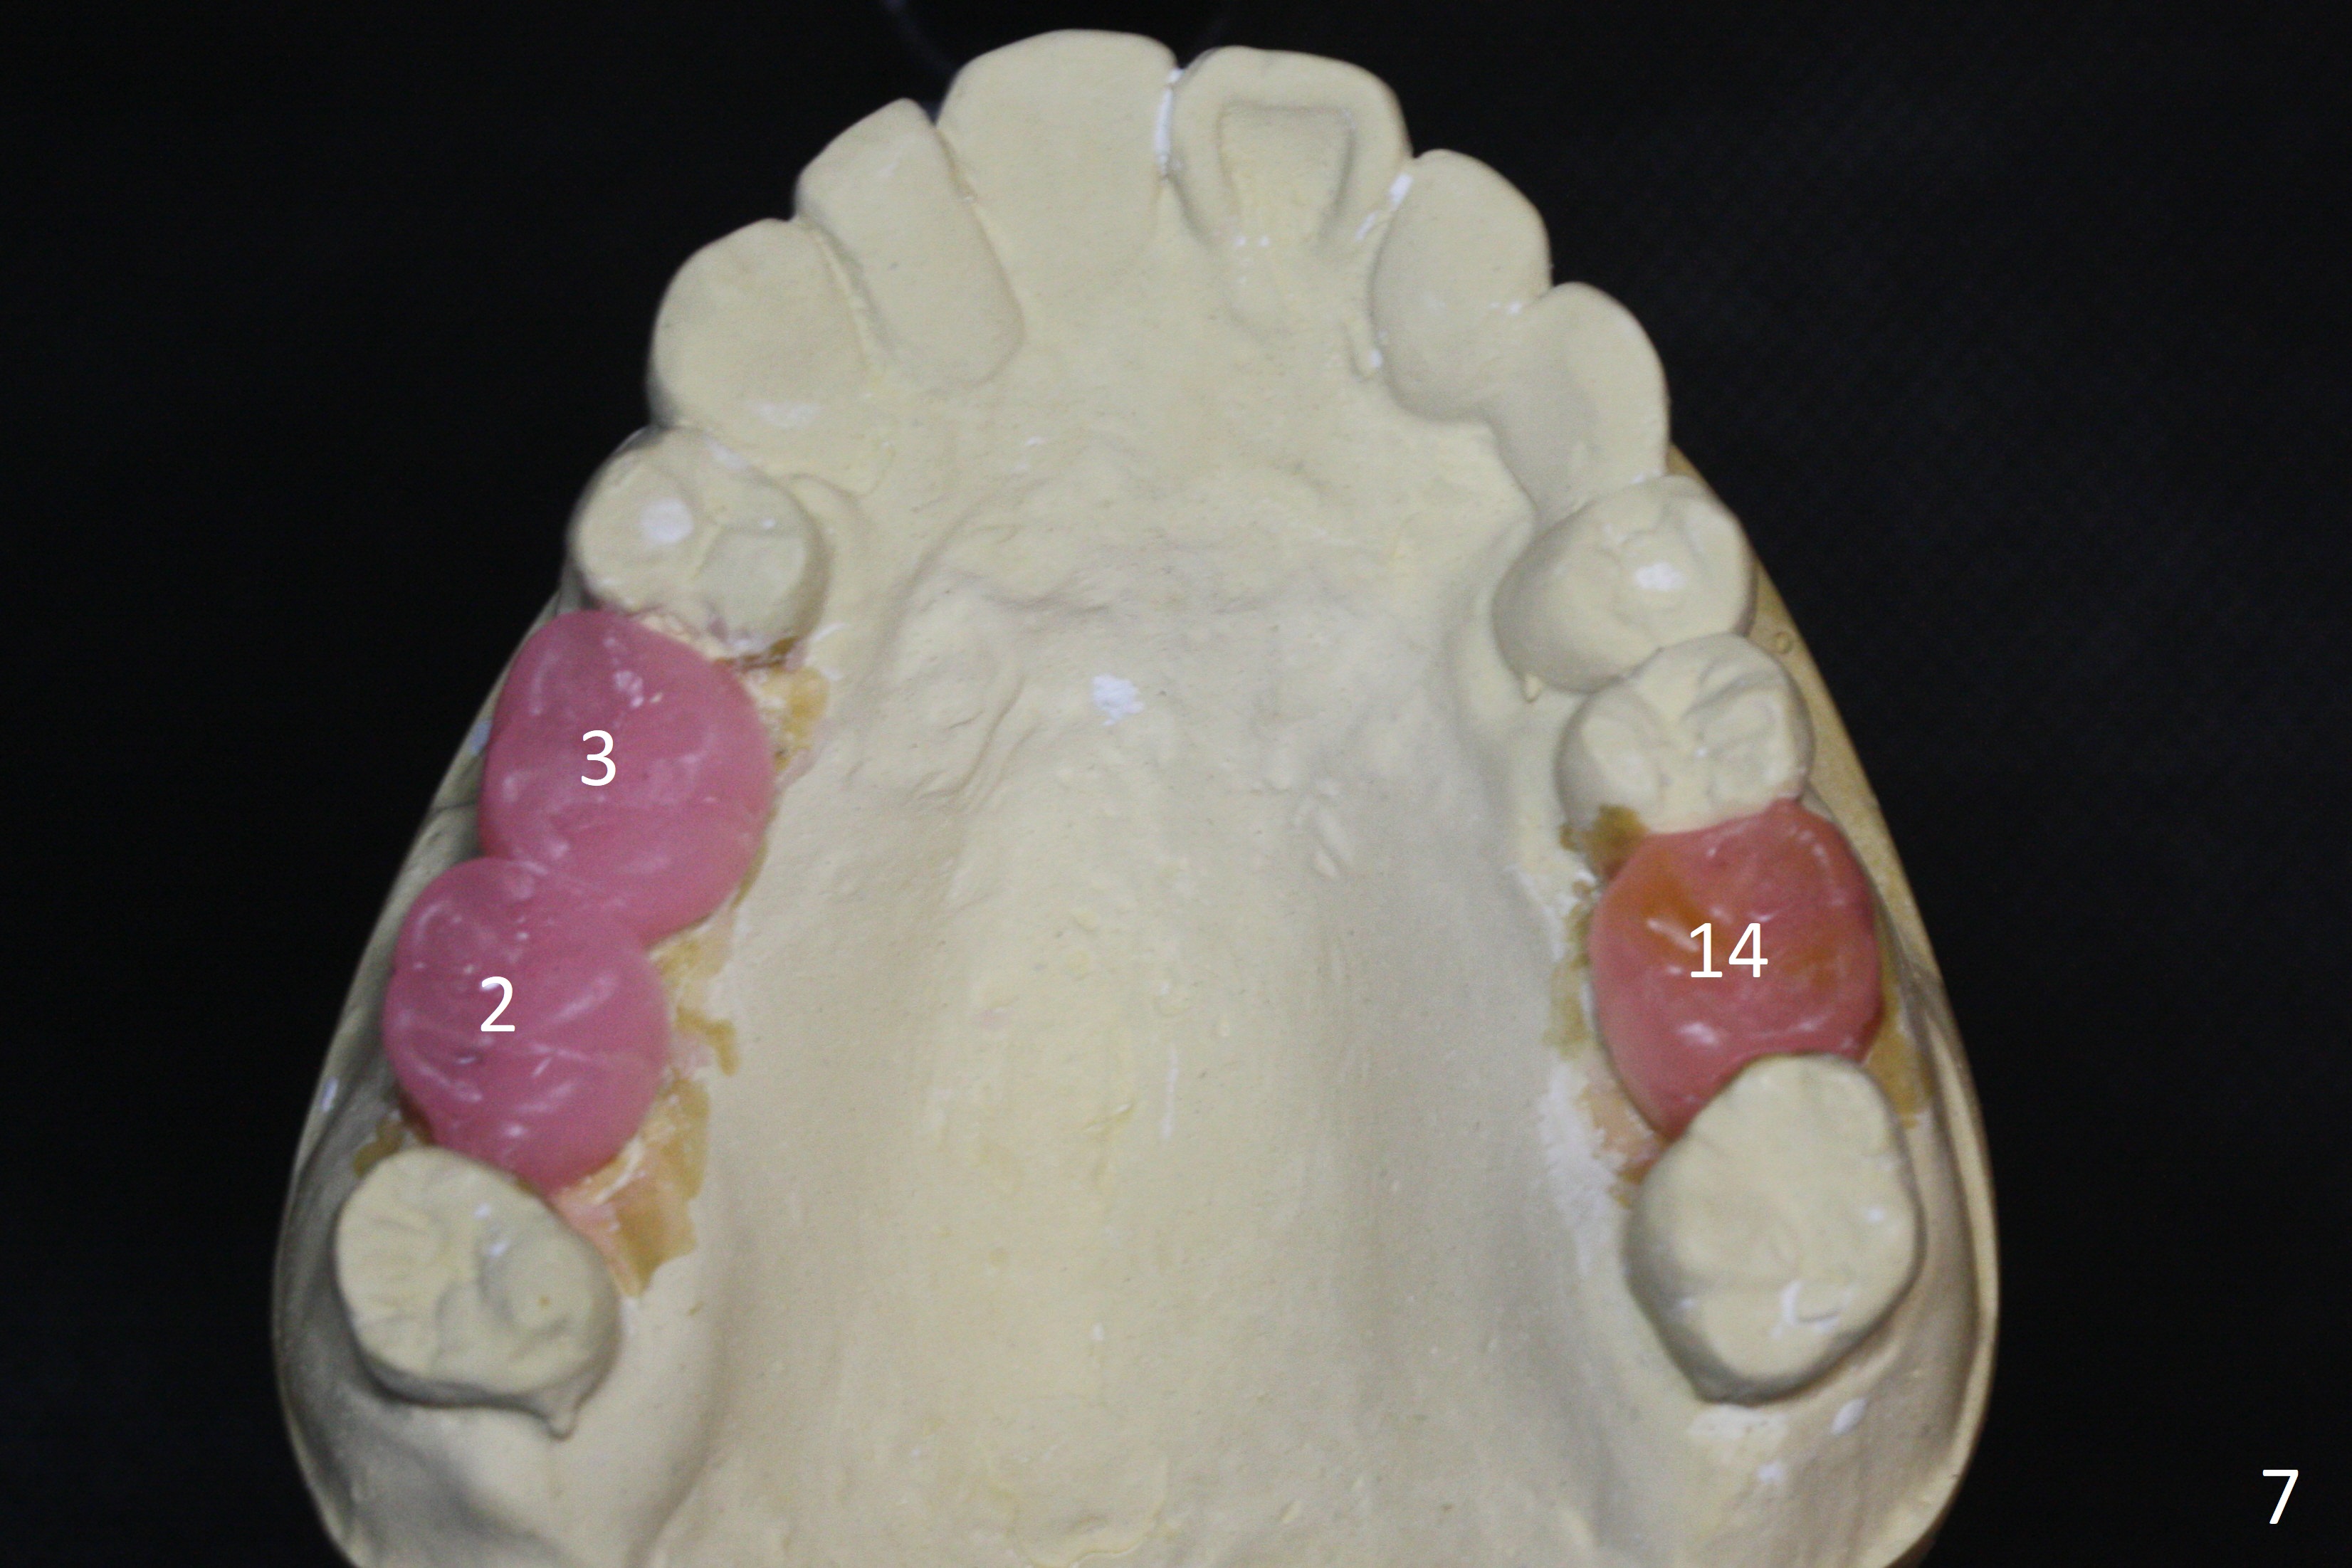

A 54-year-old man is 5 years post liver cancer surgery. After his platelet count returns normal, he wants to take care of his teeth. Most of his molars (#14, 19, 30,31) need extraction and implant placement (Fig.1-4). Although the 2nd premolars on the right are missing (Fig.1,3,4), it seems appropriate to establish 2 molar occlusion on the right (Fig.5,7,8) and 1 on the left (Fig.6,7 (because of #15 supraeruption (Fig.2 arrow))) . Since the residual roots in the lower right quadrant are irritating, implant placement will be done first (Fig.11, Clindamycin), followed by #2,3 (Fig.10) and 14(Fig.12 IBS) and 19 (Fig.12). Use IS drills and 4 and 5 mm stoppers to start osteotomy at #30 and 31, respectively.